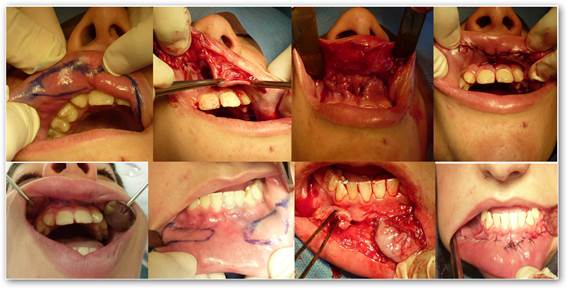

The patient is a 14-year-old male (Fig. 1) referred by the Clinic of Periodontics of the School of Dentistry to the Department of Oral & Maxillofacial Surgery III, Universidad de la República, because his upper and lower lip were enlarged, and this greatly affected him psychologically in his relationships. The enlargement had become very noticeable four years before. He visited several medical specialists and dentists that could not make a positive diagnosis or suggest a treatment plan.

The visual examination of the area showed bilateral enlargements in the upper and lower lips, which were strongly noticeable when the lips were not in resting position. The enlargements involved the mucosal aspect of both lips, were elliptical in shape with the major axis parallel to the free edge of the lip. Enlargements were found in each hemilip. The mucosa covering them was normal in color and texture, and they were painless and soft to the touch. There was no family history of this kind of malformation.

In the first stage we resected the upper lip enlargements (Fig. 3) and also performed a frenectomy of the upper lip for orthodontic reasons.

In the second stage, thirty days later, the surgical procedure was performed in the lower lip.

Both surgeries were performed using elliptical excision techniques with cold scalpel and the affected areas were sutured using separate stitches (Fig. 3).

Macroscopically, in the upper lip it can manifest as a soft, mobile, overhanging mass which on occasion can extend from one commissure to the other, or can frequently be divided in the middle by the labial frenum, resulting in two globular or oblong, middle-sized masses1.The latter applies to the case presented here.

In the lower lip (very uncommon) it almost exclusively appears as two middle-sized bun-shaped masses, as shown in the patient’s photograph.

It can exceptionally be found in both lips1,4,14, as in this patient.

As it was explained above, in this case we planned to resect in a first stage the upper lip enlargements and, on the following month, in a second surgical stage, those in the lower lip.

Both procedures were conducted using locoregional anesthesia.

We used elliptical excisions for both lips, suturing the affected areas using separate stitches, as described by Digman21 Fig. 3.

We also performed a simultaneous labial frenectomy in the upper lip, as indicted by the treating orthodontists.